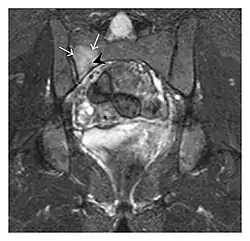

- a

- b

Figure 13: Partial osseous avulsion of the gluteal muscles at the greater trochanter in a 59-year-old man who presented with the right hip pain without a history of trauma. Lauenstein view and anteroposterior and radiographs (not shown) did not show an obvious fracture line or disruption of bony contours in the acetabulum or the right femoral neck. (a) Coronal T1-weighted MRI displays an incomplete fracture line extending partially from the greater trochanter (arrow). (b) Coronal short tau inversion recovery MRI shows heterogeneous hyperintensity in the same region (arrow) as well as hyperintensity within the gluteus medius and minimus muscles (arrowheads) consistent with tissue edema and hematoma.[1]